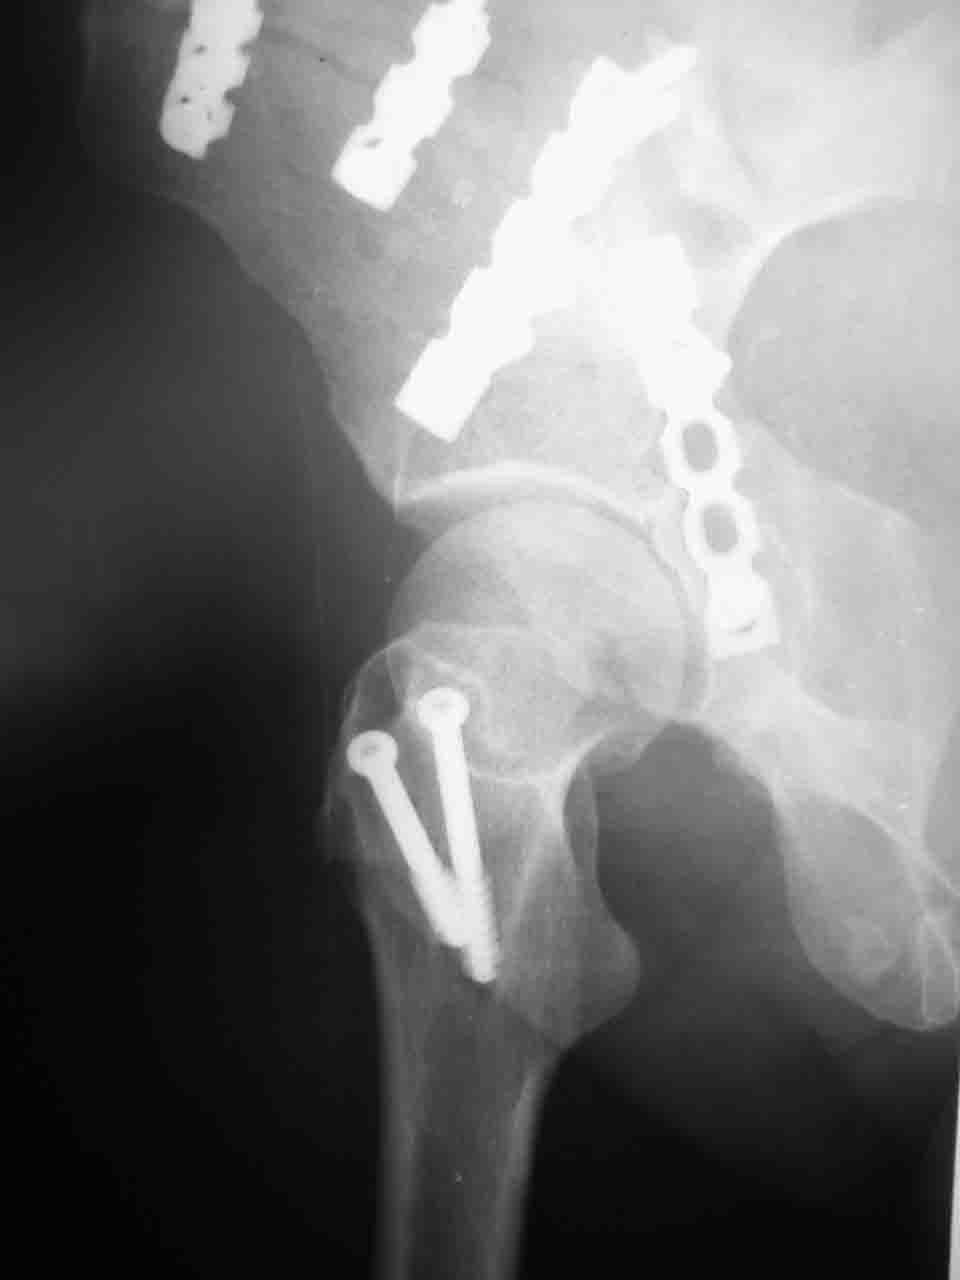

форуме и скелетном вытяжении. С репозицией и фиксацией задней колонны и отдельно задне-верхней стенки впадины проблем не возникло. Послеоп. Рг граммы в приложении. Если возникнут какие-либо дополнения или поправки - был бы признателен.

Спасибо за комментарии и рекомендации. Откровенно говоря, больного я прооперировал на прошлой неделе, через 5 дней после аварии и проблем с ним пока никаких нет, на удивление при достаточно обширной диссекции (илиофеморальный доступ) болей практически нет, так что больной самостоятельно садится в кровати, выполняет активные движения в оперированном суставе, сгибая до 60 градусов пока, далее с ассистенцией.

Причиной обращения к сообществу были возникшие непосредственно после операции сомнения и разочарования полученным качеством репозиции: а надо ли было трогать перелом вообще, репозиция передней колонны технически была очень сложна для меня, хотя реконструкции была в той же последовательности, что Д-р А.В.Рунков рекомендовал, в какой-то момент безуспешных манипуляций стал думать о *вторичной конгруэнтности*, которую не так давно обсуждали на